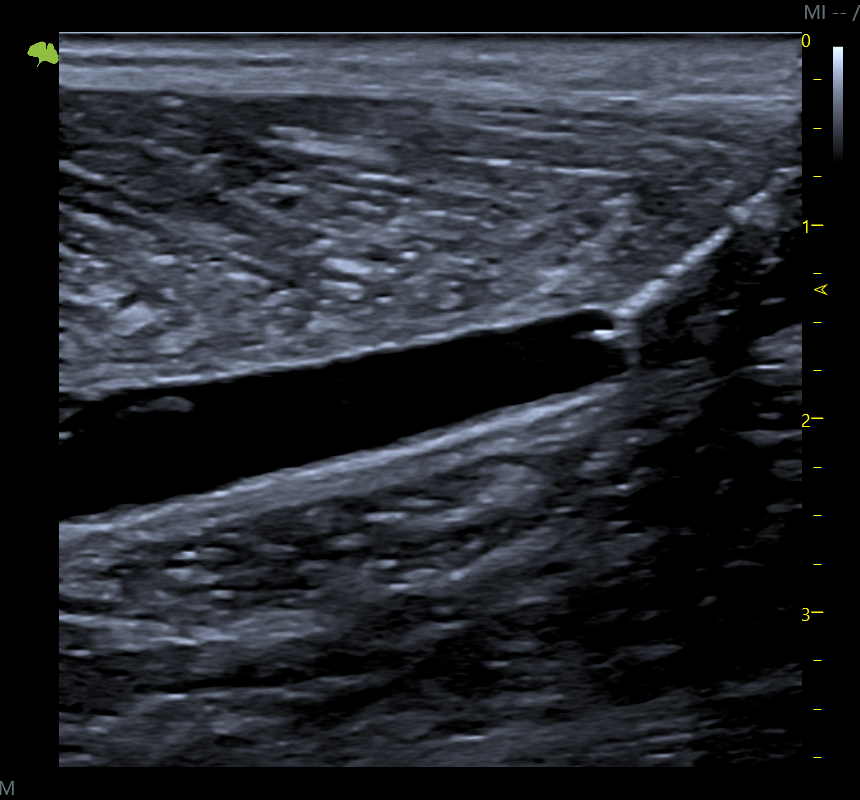

Evaluamos tu lesión en tiempo real, con máxima precisión y sin desplazamientos. Analizamos músculos, tendones y articulaciones para diseñar un tratamiento totalmente personalizado y más eficaz. No trabajamos a ciegas: vemos lo que ocurre y actuamos con exactitud para acelerar tu recuperación.